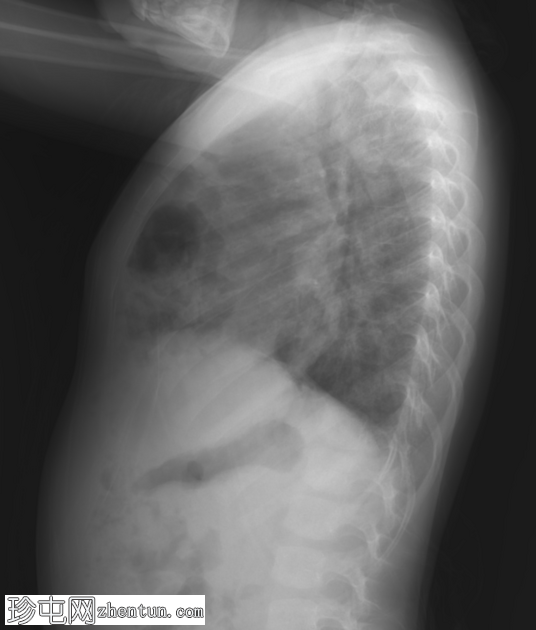

X线片

1.png

正位片

2.png

侧位片

底部可见边界不清的阴影,最符合呼吸道感染的表现。

正位和侧位片上偶然发现胸骨后肠管。